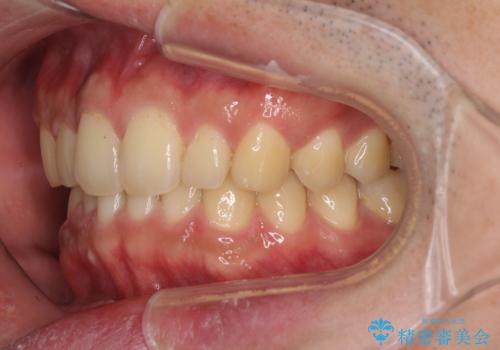

- 上下前歯のデコボコと下の前歯が隠れるほどの深い咬み合わせを気にして来院された患者様です。

インビザラインによる上下歯列の拡大と、IPR(歯と歯の間を削る)にるスペースの獲得により、口元のデコボコとディープバイトを改善することとしました。

デコボコがなくなったことで日頃の清掃が行いやすくなり、深い咬み合わせが改善したことで、食いしばりによる顎の負担も軽減されました。